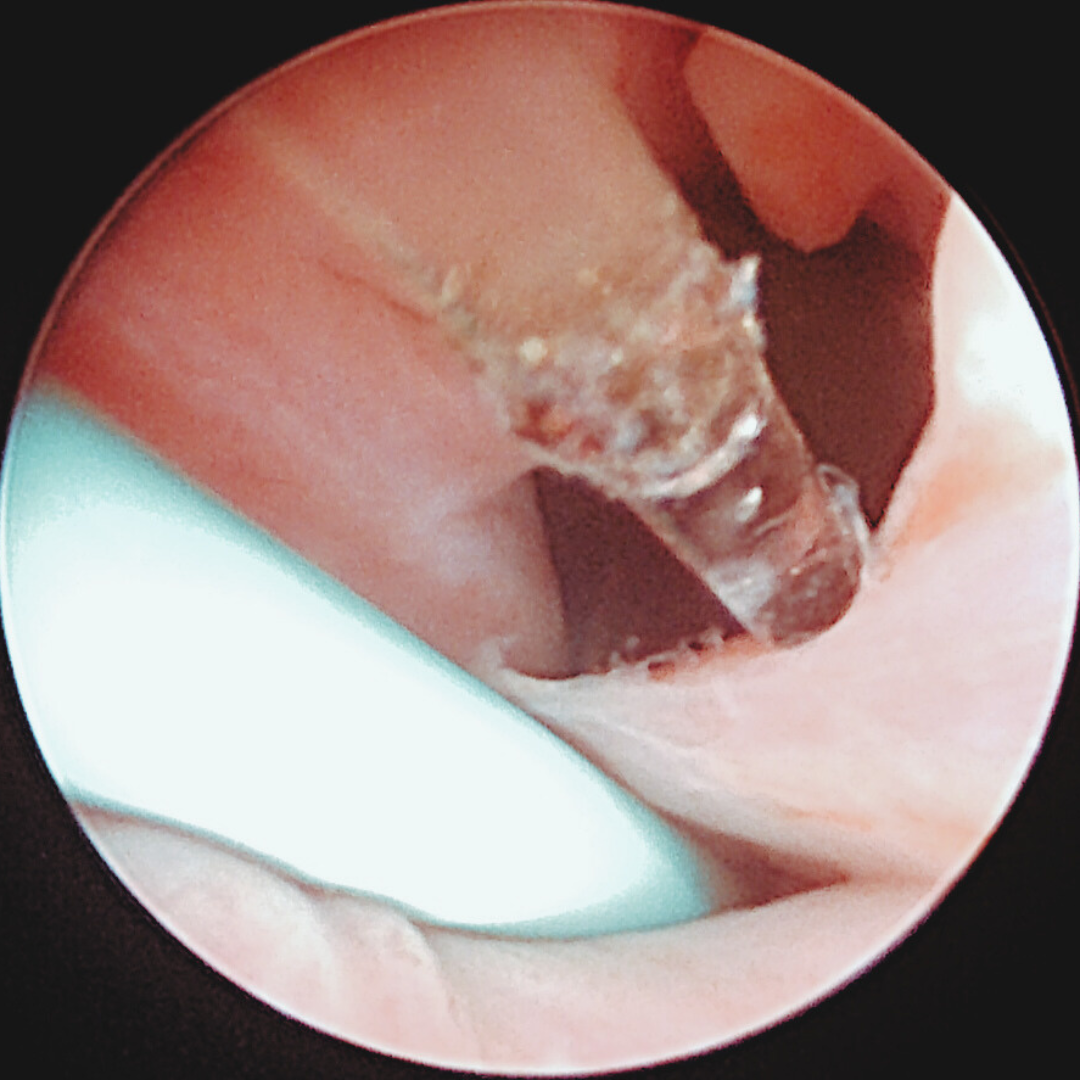

• Tracheoskopi med stentplacering

– vid trachealkollaps eller trachealstenos